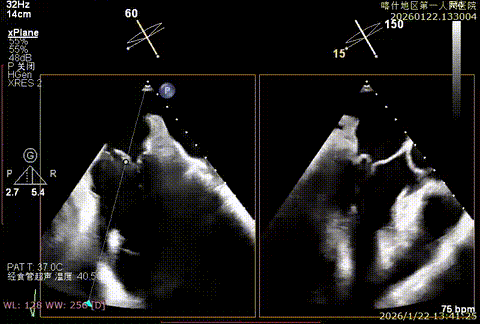

X-plan重度反流

3D enface后叶栓系

3D enface观察反流